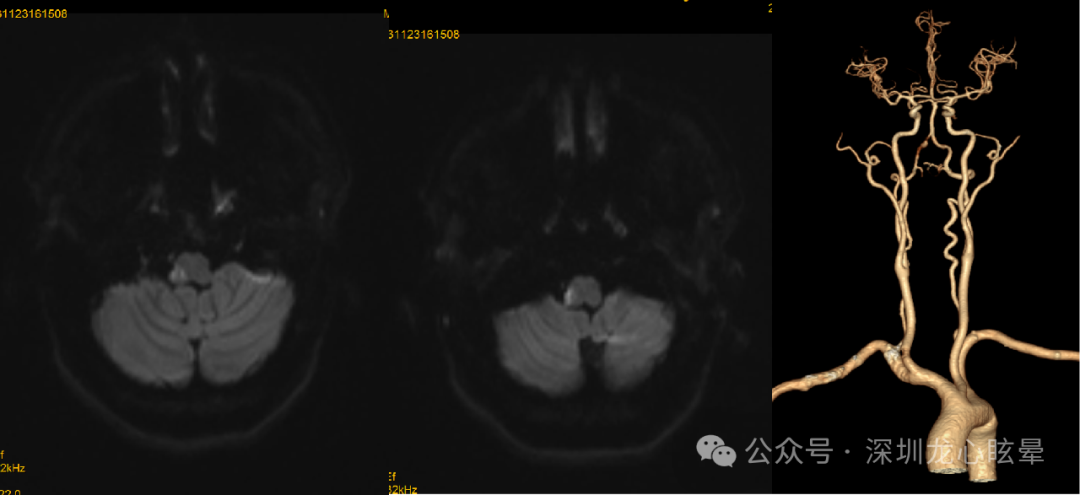

脑干病变引起血管源性头晕/眩晕:支配眼动与姿势平衡的神经整合中枢及传导束主要位于延髓背侧、脑桥被盖与中脑顶盖等区域。这一区域血供丰富,来自延髓外侧动脉、AICA、PICA的诸多分支在此形成吻合支,单纯的小梗死灶在临床较为少见,但该区局限性小梗死灶一旦出现,临床上常以类似前庭神经炎的症状就诊。脑干区域虽较为狭小,但重要核团众多,与人体平衡感知、前庭眼动反射相关的诸多核团均位于该区,如前庭神经核群、第8颅神经在脑桥延髓交界处出入脑干段区、眼动控制核团(如舌下神经前置核、Roller核、闰核、旁中央束细胞组)等,上述部位病变除了引起头晕、眩晕及失衡症状外,通常伴随邻近结构损害相关症状和体征,需重视神经系统查体以及脑干综合征的识别(延髓背外侧综合征、延髓内侧综合征、脑桥被盖下部综合征、核间性眼肌麻痹等)。若病变仅损害延髓-脑桥背侧的前庭神经核、舌下周核复合体或第Ⅷ对脑神经延髓-脑桥交界入颅段可表现为中枢性血管源性头晕/眩晕,其中 REZ区域因供血动脉吻合支丰富,梗死较为罕见。

图3 一例右侧延髓急性脑梗死(椎动脉夹层)

(5)孤立性前庭神经核梗死:前庭神经核是一组核团,包含内侧核、外侧核、上核、下核4部分,其中位于脑桥下部的4个核团由 AICA 供应,而位于延髓上部的前庭神经内侧核和下核由 PICA 供应。前庭神经核受损可能同时表现为外周和中枢前庭病变的特征,使诊断极具挑战性。可表现类似前庭神经炎的孤立性眩晕,朝向健侧的水平-扭转自发眼震,固视可抑制,去除固视眼震增强,患侧水平 HIT及双温试验阳性、患侧前庭肌源性诱发电位减低或引不出,早期头颅 MRI正常。但同时患者又表现出凝视诱发的变向眼震(中枢前庭受损的表现),显示神经整合器功能障碍(水平眼动的神经整合是由前庭内侧核、舌下神经前置核和绒球共同完成)。患者复查头颅 MRI显示单侧前庭神经内侧核和下核梗死。

(6)孤立性 NPH 梗死 : NPH 由来自基底动脉的穿支动脉及来自盲孔浅动脉的前内侧长动脉供应。NPH 与前庭内侧核、内侧纵束、旁正中网状结构相邻,是水平眼动的神经整合器,参与视动通路,协调头部和躯干运动。孤立性 NPH 受损常表现为朝向患侧的自发眼震;GEN(在注视患侧时眼震增强)。患侧扫视正常,但平稳跟踪异常;床旁 HIT 阴性,双温试验正常。可向健侧倾倒。